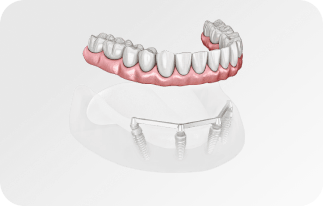

Зубы за 1 день за 5776р. в месяц

с пожизненной гарантией

По уникальной методике

БЕЗ отёков и надрезов

Установка

за 1 день